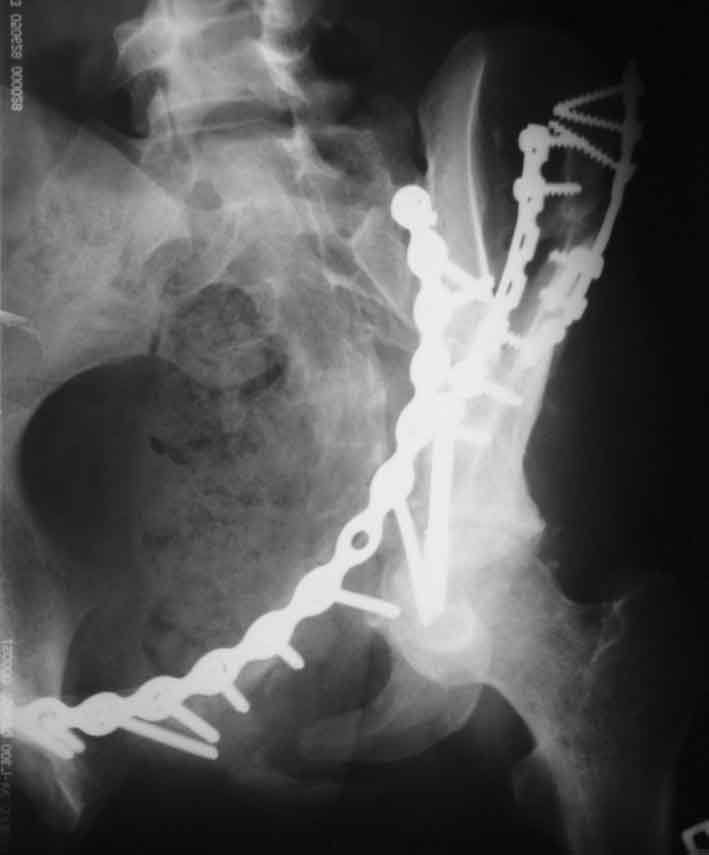

Рентгенограммы после операции

подвздошная